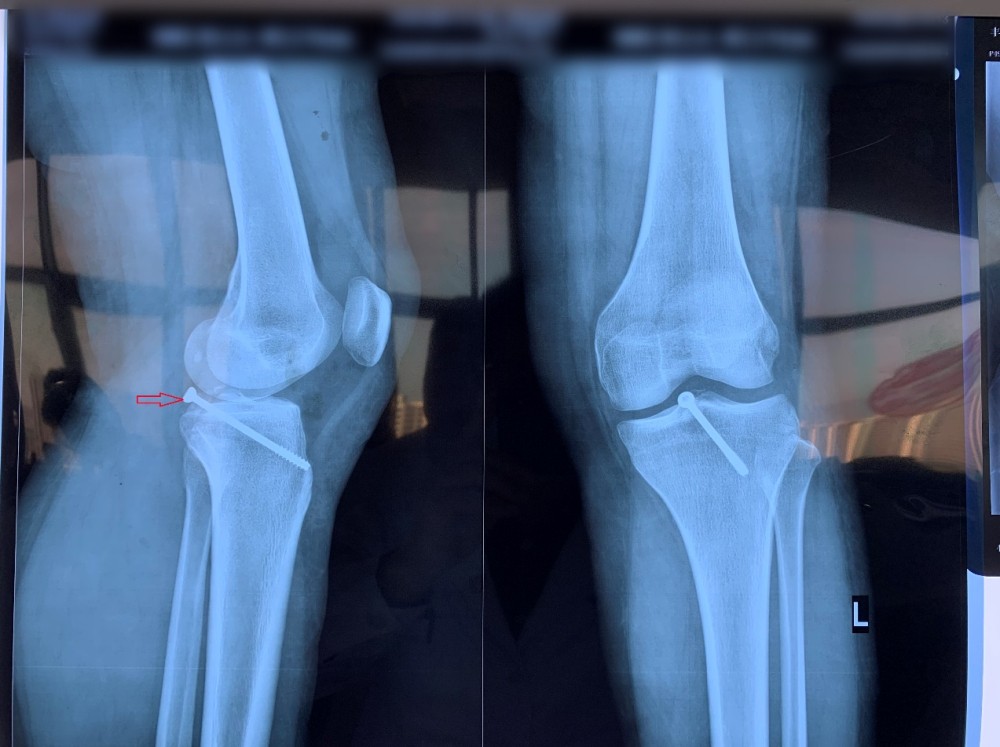

患者因外伤导致左胫骨髁间棘骨折,骨折移位明显,具备手术指征。但患者为年轻女性,担心手术瘢痕影响美观,传统手术方式无法满足患者需求。综合考虑后,91直播 创伤外科中心王建忠教授团队为患者制定了应用骨科手术机器人辅助下进行微创手术的诊疗方案。通过机器人进行数据采集、手术规划等人工智能手段,术中仅用约2cm切口即成功完成手术。与传统手术相比,此类手术切口明显减小,出血量少,达到了微创、精准的手术效果,患者及家属非常满意。

术后X线片